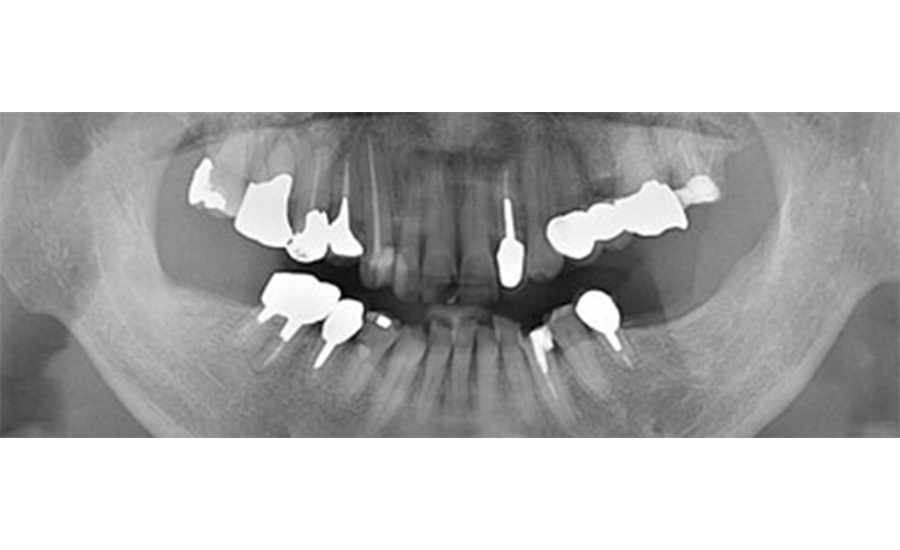

主に歯や歯を支えている骨の把握と顎の関節の状態などをチェックします。

| ③デンタル10枚法: | レントゲン撮影でお口の全体像を把握して、 この10枚法にて歯1本1本について問題がないか詳しく調べます。 |

レントゲン撮影でお口の全体像を把握して、この10枚法にて歯1本1本について問題がないか詳しく調べます。